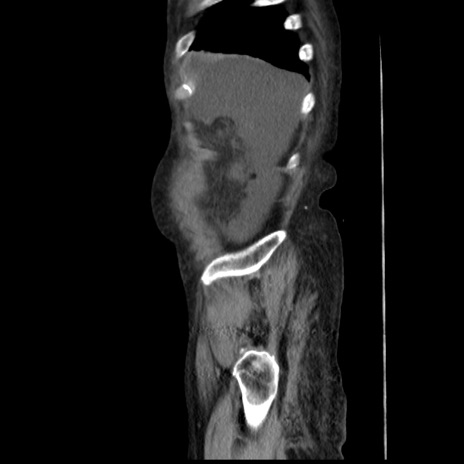

症例31(矢状断像)

【症例】80歳代 女性

【主訴】腹部膨満感

【現病歴】他院にて肝硬変にてフォロー中。1週間前から便秘、腹部膨満感、臍部腫瘤あり受診となる。

【既往歴】肝硬変

【身体所見】腹部膨隆あり、皮膚変化なし、疼痛なし。

【データ】WBC 4600、CRP 0.25